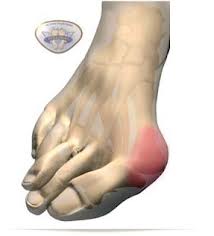

Вальгусная деформация большого пальца стопы (Hallus valgus) - это состояние, при котором происходит повреждение сустава большого пальца ноги. Это заболевание обычно называют бурситом большого пальца, который связан с образованием костного нароста. Появление его свидетельствует о неправильной работе стоп, часто связанной с плоскостопием. Нарушение мышечного баланса также может привести к возникновению "косточки" и отклонению большого пальца. Сначала возникает только косметическая проблема, серьезный дискомфорт может развиться со временем.

Симптомы вальгусной деформации: деформированный, кривой большой палец стопы; в области сустава припухлость в виде шишки; боль и покраснение вокруг сустава ; возникают проблемы при ношении обуви; на шишке возникают мозоли.

Симптомы: искривление большого пальца ноги, припухлость сустава, боль и покраснение вокруг сустава большого пальца, мозоли на суставе большого пальца стопы